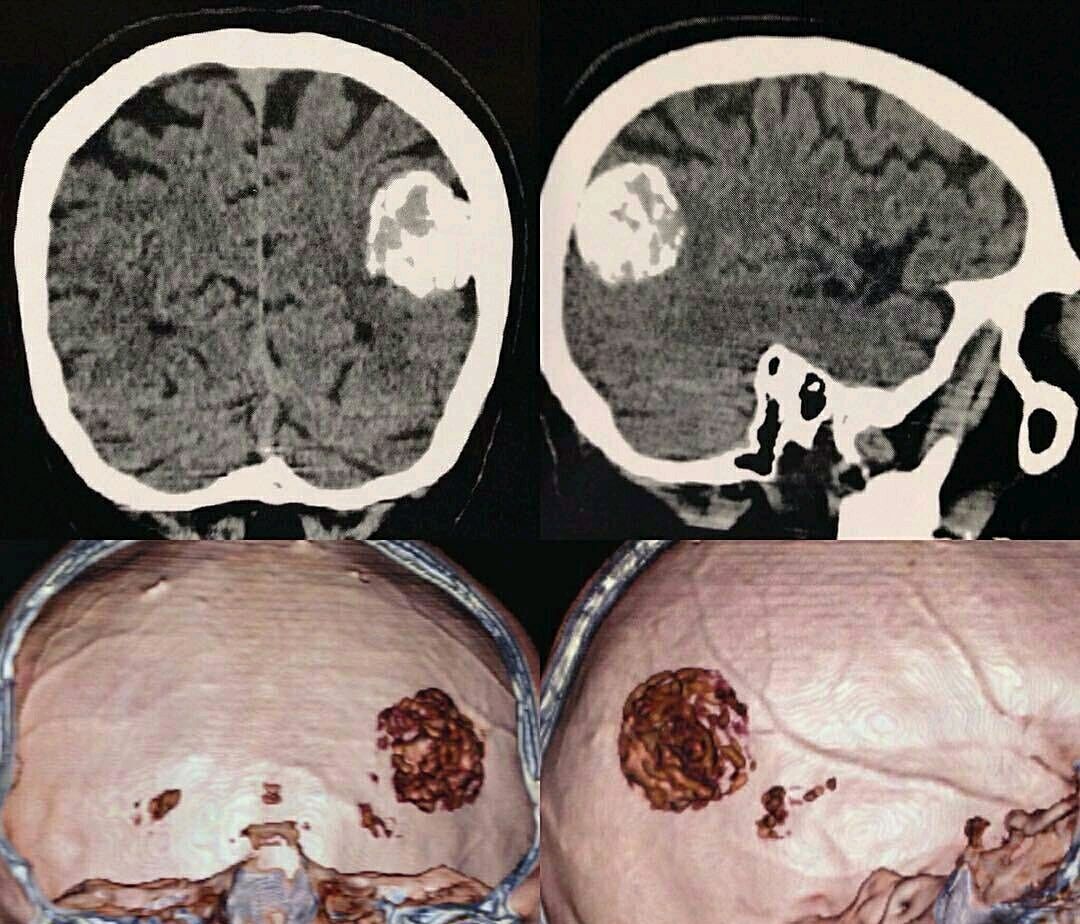

图片尺寸1080x924

下面为经我手术的典型部位脑膜瘤手术前后对比

图片尺寸610x435